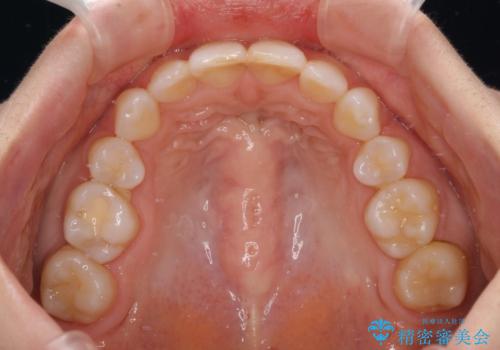

奥歯の咬み合わせ改善には1年ほどの期間と処置中の噛みにくさを強いることとなりましたが、抜歯後はスムーズに治療を完了させることができました。

歯ぎしりの際に奥歯が干渉していた咬み合わせも理想的な状態に改善できました。